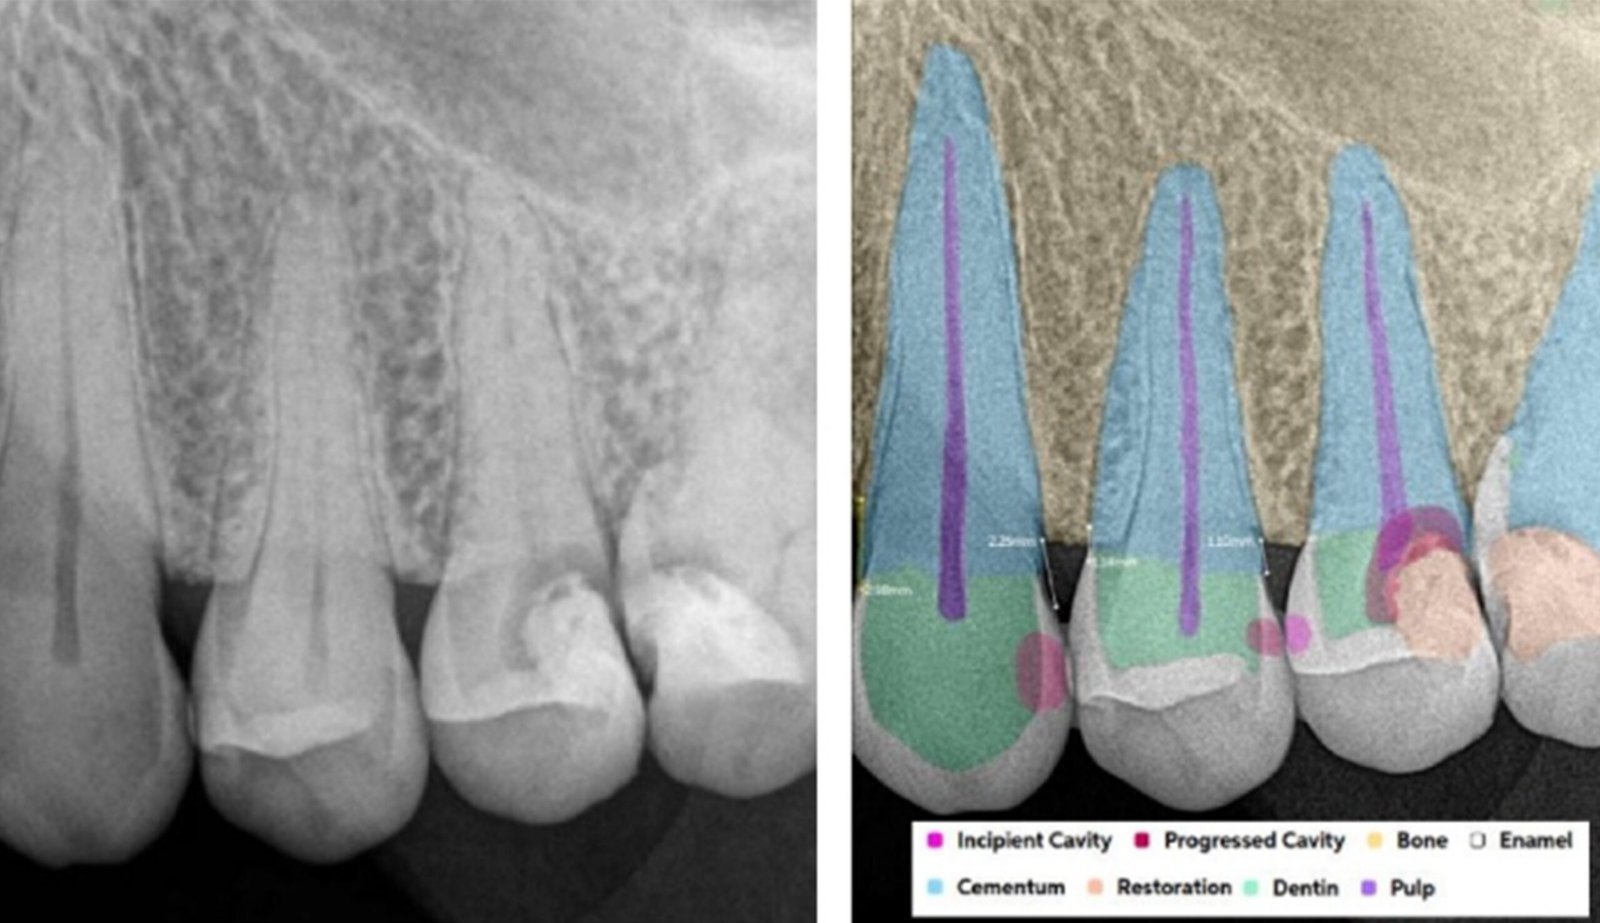

Leveraging AI-driven simulations, this segment integrates predictive modeling with clinical design. We optimize prosthetic, implant, and restorative solutions by forecasting mechanical performance, identifying risk areas, and supporting data-driven treatment planning.